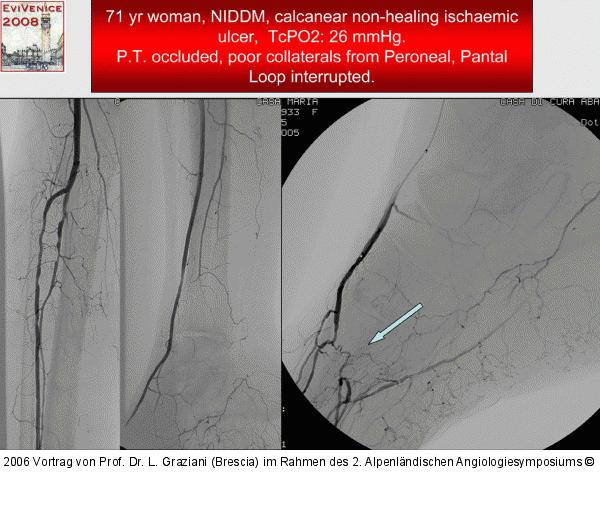

Vortrag von Prof. Dr. L. Graziani (Brescia) im Rahmen des 2. Alpenländischen Angiologiesymposiums

PTA of the foot arteries in diabetics: Extremities Extreme Angioplasty

Abbildung 62: P.O.B.A.